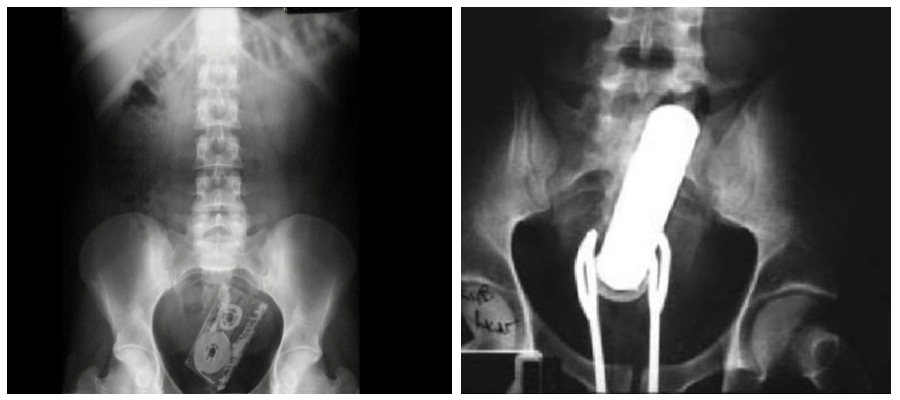

L’uomo ha chiesto assistenza soltanto due ore dopo aver inserito il flacone, presentandosi al Pronto soccorso con un “dolore addominale acuto”. I raggi X hanno poi rivelato le cause, dietro l’incredulità di medici e chirurghi che hanno praticato un’incisione rimuovendo il flacone. L’uomo, dopo l’episodio, ha promesso di non far più di testa sua.